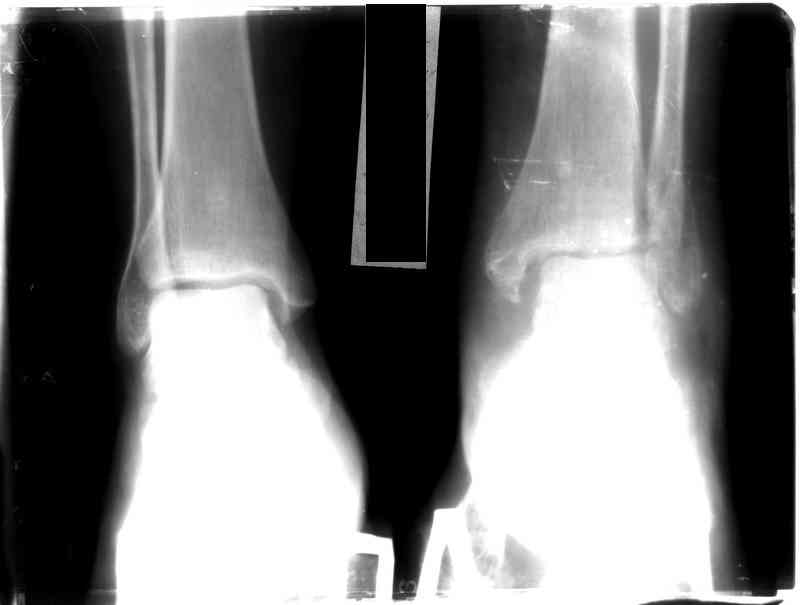

Перелом обеих лодыжек и з/края б/б кости с вывихом стопы,new |

Ув. коллеги, я уже сообщал об этом случае недавно. Металлоконструкции удалены через 7 недель с момента травмы, после чего еще месяц иммобилизации, осторожная дозированная нагрузка. Спустя 3,5 месяцев имеем следующее. Что порекомендуете? С ув. Sergey A. Melashenko ул. Кирова 88-А, г. Приморск, Запорожская обл., 72100, Украина

Ув. Максим. Движения в суставе в полном объеме, беспокоят выраженные боли в суставе, сохраняется отек. Осевая наргрузка болезненна, особенно

в проекции синдесмоза. Похоже вся проблема в синдесмозе. Может обождать, пока окрепнет наружная лодыжка и провести операцию, как при застарелом

повреждении синдесмоза (болт-стяжка или что-нибудь поновее)